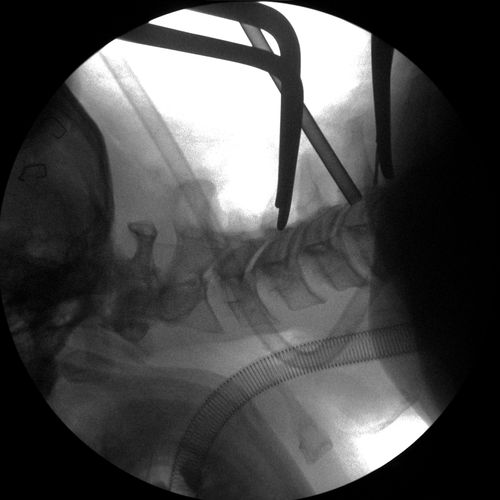

Anterior Cervical Discectomy & Fusion

Cervical Spine Fixation